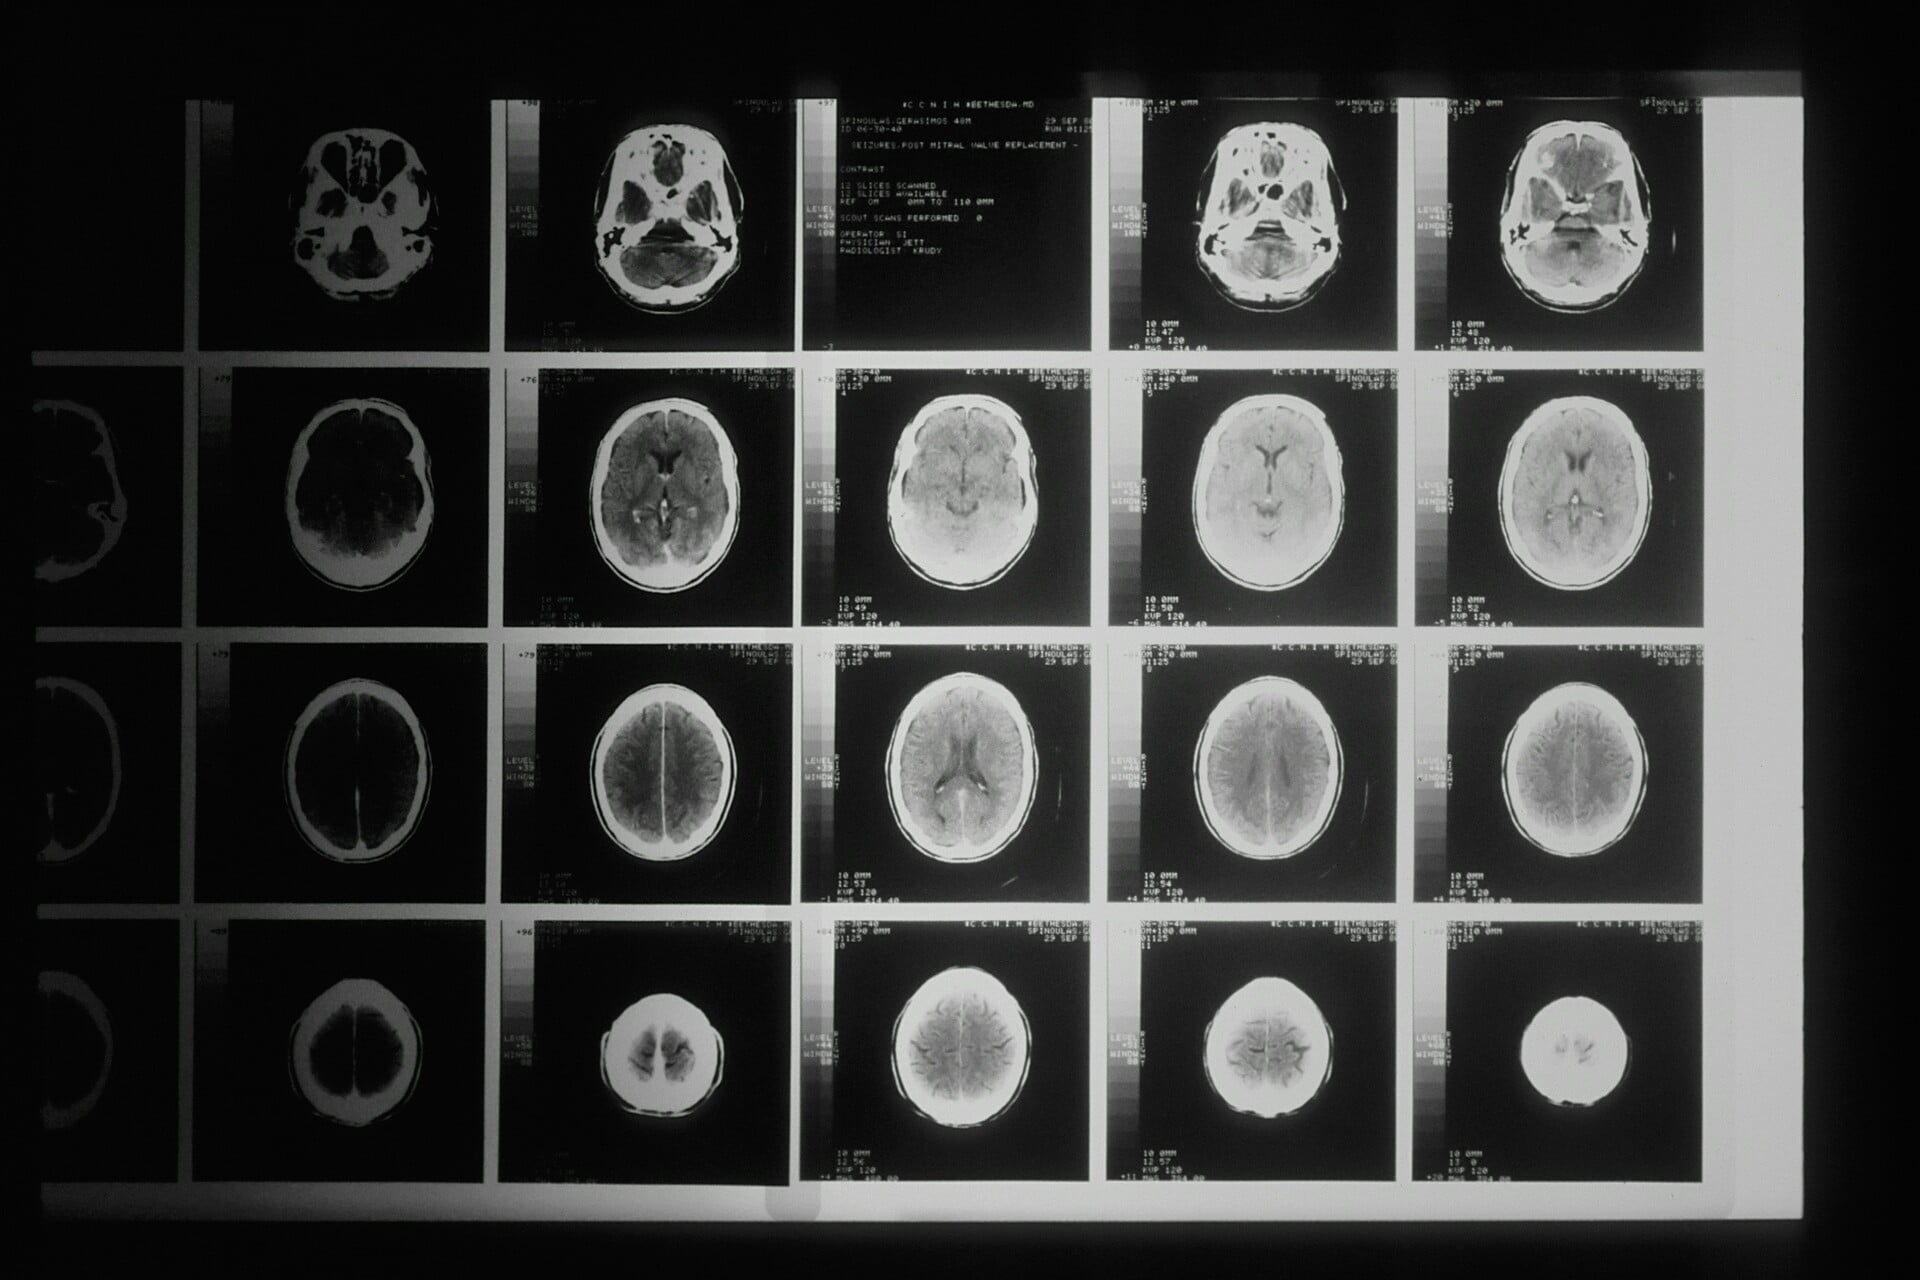

Φωτογραφία: Unsplash

Τα ευρήματα δείχνουν ότι οι εξετάσεις αίματος μπορεί να είναι πιο ευαίσθητες από τις εγκεφαλικές απεικονίσεις στο να εντοπίζουν πώς η παχυσαρκία επηρεάζει τα πρώιμα στάδια της άνοιας, ανέφεραν οι ερευνητές.

«Το γεγονός ότι μπορούμε να παρακολουθούμε την επίδραση της παχυσαρκίας στην αύξηση των βιοδεικτών στο αίμα ακριβέστερα από ό,τι με PET (ποζιτρονική υπολογιστική τομογραφία) ήταν αυτό που με εξέπληξε περισσότερο στη μελέτη», πρόσθεσε.

Η ομάδα του Ράτζι παρακολούθησε 407 άτομα για πέντε χρόνια, χρησιμοποιώντας δείγματα αίματος και σαρώσεις PET για να εντοπίσει σημάδια Αλτσχάιμερ. Οι σαρώσεις PET μετρούν τη συσσώρευση πλακών αμυλοειδούς στον εγκέφαλο — ένα βασικό χαρακτηριστικό της νόσου — ενώ οι εξετάσεις αίματος δείχνουν τα επίπεδα πρωτεϊνών και άλλων βιοδεικτών που σχετίζονται με γνωστική έκπτωση.

Ο Ράτζι δήλωσε ότι τα ευρήματα θα μπορούσαν να βοηθήσουν τους γιατρούς να παρακολουθούν την εξέλιξη της νόσου με την πάροδο του χρόνου. Για παράδειγμα, οι βιοδείκτες αίματος και οι εγκεφαλικές απεικονίσεις θα μπορούσαν να τους βοηθήσουν να αξιολογήσουν την αποτελεσματικότητα φαρμάκων που στοχεύουν στη μείωση του αμυλοειδούς, είπε.

«Είναι υπέροχο που διαθέτουμε αυτούς τους βιοδείκτες αίματος για να παρακολουθούμε τη μοριακή παθολογία της νόσου Αλτσχάιμερ, καθώς και μαγνητικές τομογραφίες για να καταγράφουμε επιπλέον ενδείξεις εκφύλισης του εγκεφάλου και ανταπόκρισης σε διάφορες θεραπείες», είπε ο Ράτζι.